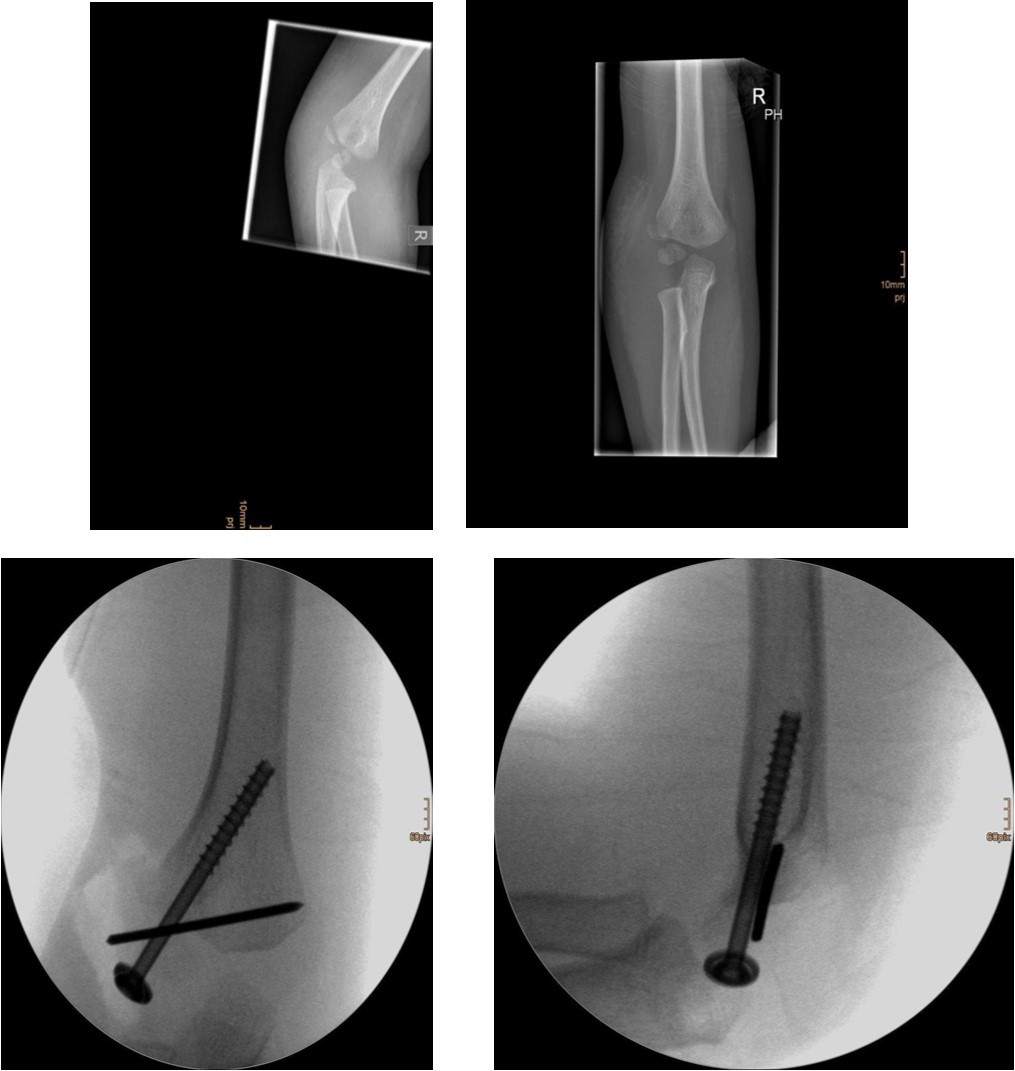

Figure 2.6 year old male patient with a dislocated right lateral condyle fracture which was treated by open reduction and osteosynthesis with a screw and a Kirschner wire (personal collection)

Non-displaced and stable fractures may be treated by cast immobilization with close follow-up, but fractures displaced >2 to 3 mm may indicate surgical fixation 7, 8. Surgical treatment can be done either by closed reduction and percutaneous osteosynthesis or open reduction and osteosynthesis. Figure 3.